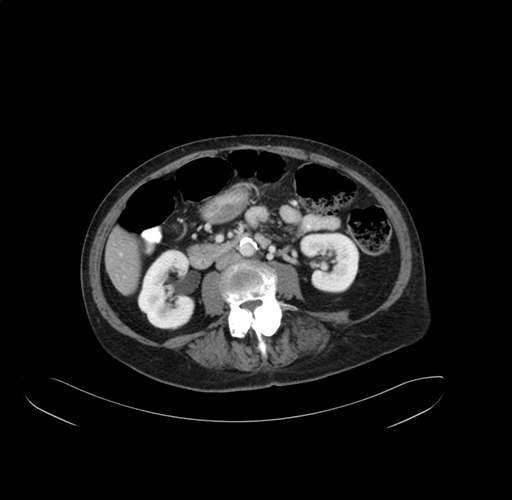

Axial Venous